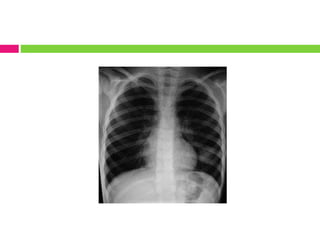

La bronquiolitis es causada principalmente por el virus sincitial respiratorio. Afecta a niños menores de 2 años, especialmente entre los 3 y 6 meses, y se presenta típicamente en los meses de noviembre a marzo. Los síntomas incluyen rinorrea, tos, fiebre y dificultad respiratoria progresiva. El diagnóstico se basa en la historia clínica y el examen físico, y el tratamiento consiste en hidratación, oxígeno, broncodilatadores y control de la fiebre.